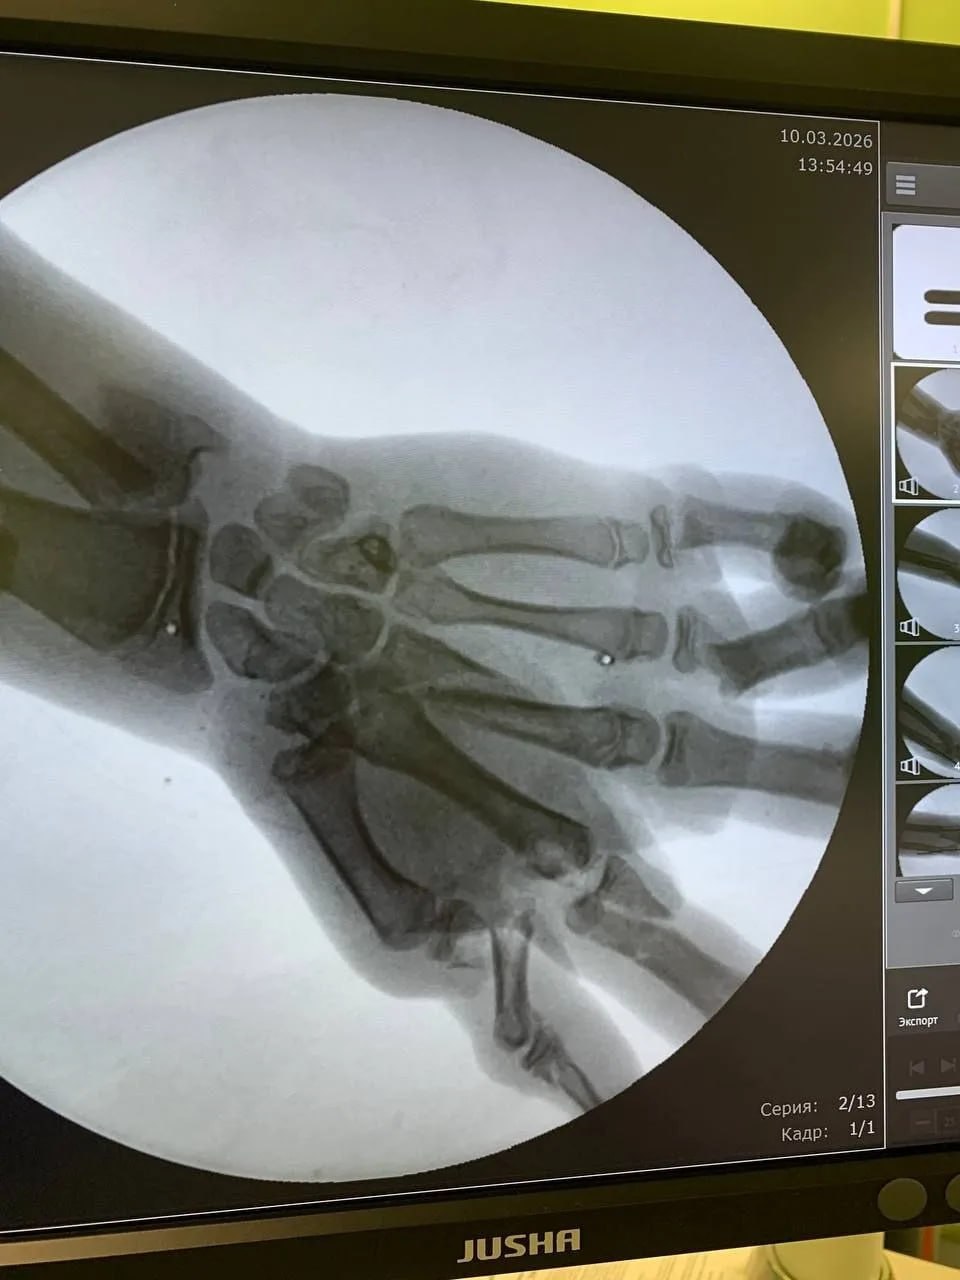

Как рассказало региональное министерство здравоохранения, подросток зачем-то распилил болгаркой снаряд во дворе частного дома. Детонация боеприпаса прошла по счастливому сценарию: парень мог погибнуть на месте. Однако, травмы оказались в пределах возможного для исправления врачами: перелом нижней трети левого предплечья со смещением, раны левой голени и лба. Больше всего досталось левой кисти – множественные переломы костей, кровотечение.

Для спасения конечности от ампутации ребёнка экстренно прооперировала бригада опытных врачей: хирурги-травматологи Александр Гозун, Геннадий Петров и Артём Чабан. Их поддерживал врач-анестезиолог Виктор Берг.

Операция длилась 1,5 часа. Доктора заново собрали кисть руки вместе, остановили кровотечение, но обеспечили кровоток в ней, а иначе кисть могла бы отмереть.

Через несколько дней врачи сделали вторую операцию – она была уже пластической для устранения дефектов тканей и костей.